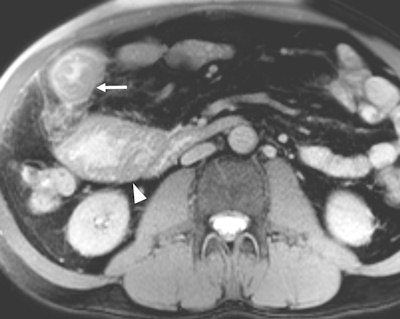

Among the bowel and mesenteric diseases to be aware of are internal hernia, intussusception, neuroendocrine tumor, and familial Mediterranean fever, all of which can mislead radiologists to erroneously diagnose active Crohn's disease, Kavaliauskiene stated. Often, knowledge of findings in these diseases can be sparse.

Peritonitis, or serositis, of small bowel loops may occur in common diseases causing acute abdominal pain (e.g. appendicitis), in postsurgical patients and in rarer diseases such as familial Mediterranean fever, Kavaliauskiene wrote. This is a hereditary autosomal recessive disease with the highest prevalence in Turkey and lower prevalence in Israel, Armenia, and other Middle East countries. The fever is also found in Greece, North Africa, Italy, Germany, France, the U.S., and Japan. The prevalence of the gene associated with familial Mediterranean fever mutation in different ethnographic groups predisposes such distribution. Distribution is related to world migration as most ancient mutations appeared in the Middle East -- in the former area of Mesopotamia -- and are thought to be spread all over the world.